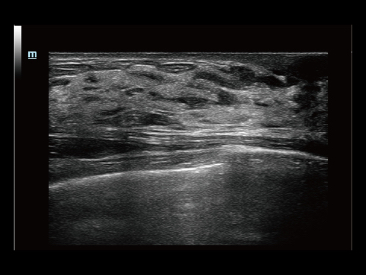

Od czasu kiedy zosta?a za?o?ona, Firma Mindray nieustannie poszukuje nowych sposob├│w na polepszenie precyzji w diagnostyce. Dzi?ki zastosowaniu najbardziej rewolucyjnej technologii ZONE Sonography? Technology, platforma ZST+ zastosowana w aparacie Resona 7 przenosi jako?? obrazu ultrasonograficznego na wy?szy poziom dzi?ki strefowemu uzyskiwaniu obrazu - zone acquisition i obr├│bkce danych kana?owych.

Oprócz uzyskiwania jako?ci obrazu typowego dla aparatów klasy premium, Resona 7 rozszerza mo?liwo?ci klinicznych badań USG dzi?ki rewolucyjnej funkcji V Flow, s?u??cej do oceny hemodynamiki naczyń, a tak?e najlepszej na rynku funkcji inteligentnego, automatycznego uzyskiwania p?aszczyzny na podstawie zestawów danych obj?to?ciowych 3D, umo?liwiaj?cej diagnozowanie stanu Centralnego Uk?adu Nerwowego u p?odu. Aparat Resona 7 ??czy w sobie najbardziej intuicyjn?, wielodotykow? obs?ug? za pomoc? gestów oraz wszystkie kluczowe funkcje kliniczne, co sprawia i? jest prawdziwym liderem we wprowadzaniu innowacji w ultrasonografii.